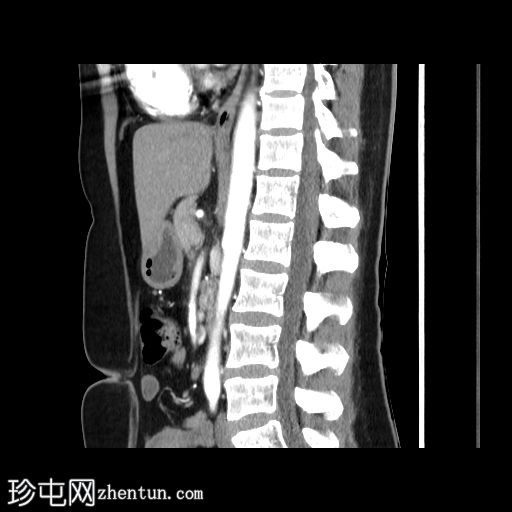

门静脉期

冠状面C+期

在轴向、冠状面和矢状面上均可见肝5/6段病变。动脉期可见周围结节状强化,门静脉期可见进行性向心性充盈,延迟期亦持续存在。这些表现为肝血管瘤的特征性表现。